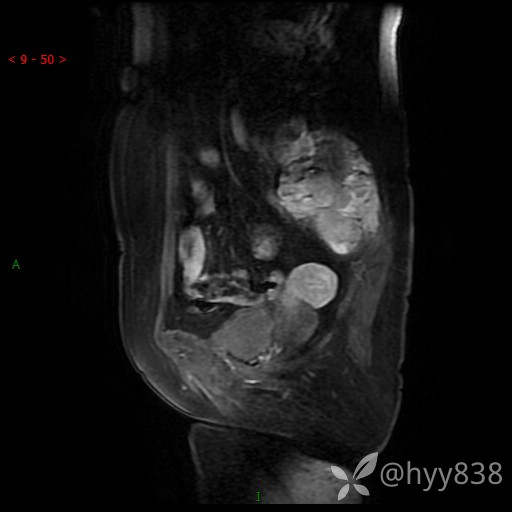

老年女性,腰痛不适就诊。少见病例,信号特征或许是一丝线索,请分析--结果公布~

简要病史:腰部疼痛不适,当地人民医院CT示骶骨骨质破坏并髂骨累及

骨盆MRI平扫(T1WI+T2WI+DWI)(外院CT,不能上传)